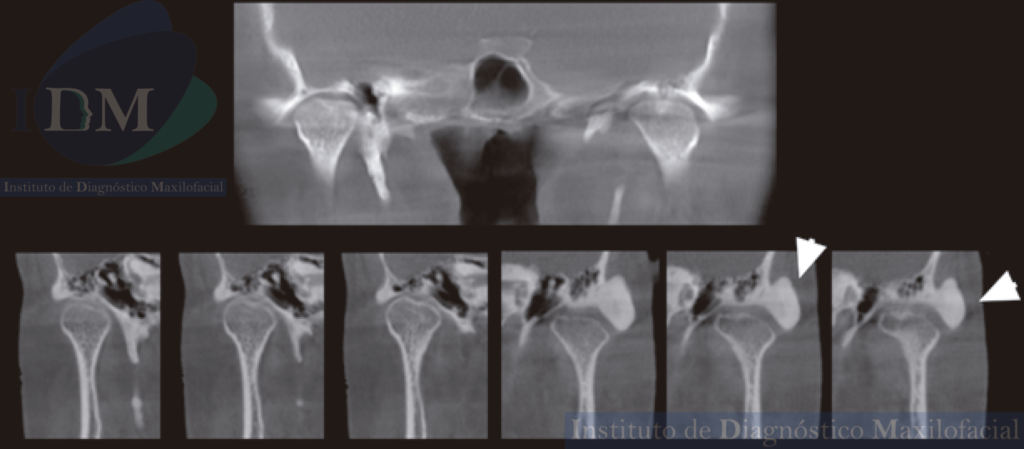

Al observar la tomografía volumétrica de haz cónico (en las reconstrucciones multiplanares, vistas transaxiales y tangenciales) se evidencia la misma imagen de forma redondeada y de densidad ósea que se localiza en la zona infratemporal y en la región posterior del arco cigomático izquierdo próximo a la cavidad glenoidea que a su vez estaría ocasionando un aplanamiento del contorno condilar en su cara externa.

ATM BOCA CERRADA

CORTES SAGITALES